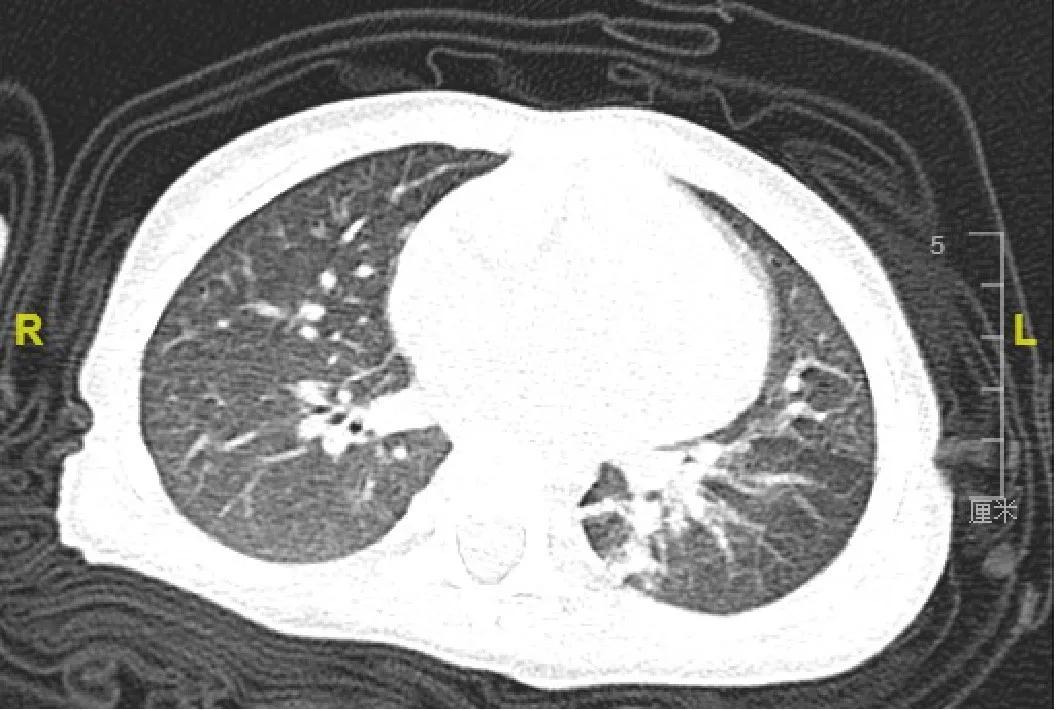

小朋友的CT

依据CT检查,仍考虑存在左下肺炎症,炎症吸收并不明显,不排除腔内异物存在。